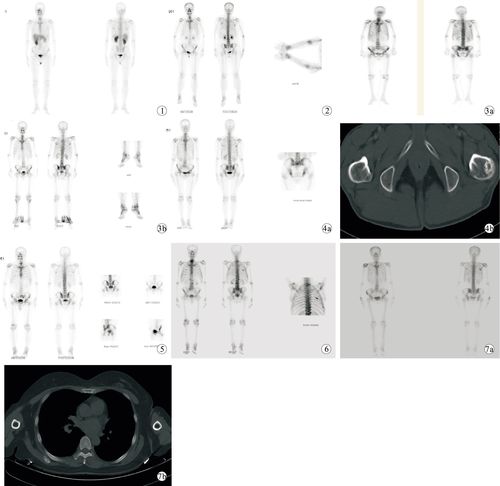

pdca循环改进方法在提高全身骨扫描图像质量中的应用

全身骨扫描报告解读一

骨扫描骨转移

骨扫描

全身骨扫描

骨扫描图片

骨扫描骨转移报告图

正常骨扫描图片

全身骨扫描图片

骨扫描显示骨转移图片

骨扫描图片怎么看

肺癌骨转移骨扫描图片